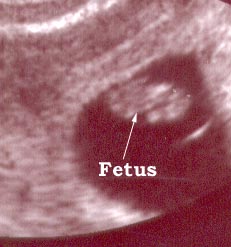

Fetus artık hem vaginal hemde abdominal( karın) ultrasonografi ile rahatlıkla değerlendirilebilir. Baş-popo uzunluğu yaklaşık 2 ila 3 cm’dir. Embrio insan şeklini kazanmıştır. Ultrasonda baş, gövde ve ekstremiteler saptanabilir. Bebeğin kol-bacak ve vücut hareketleri ultrasonda görülebilir. Fetus ekstremitelerini ve gövdesini kımıldatmaya başlar ve rahim içinde takla atarken görülebilir. Ancak anne bunu hissedemez. Cinsiyeti görebilmek mümkün değildir.